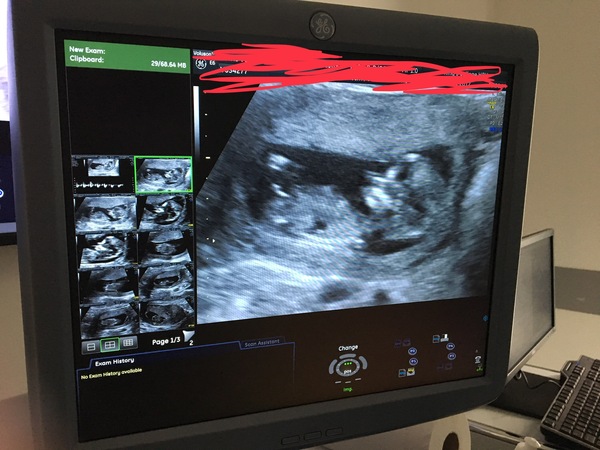

My scan went well today, one healthy baby. They've moved my dd one day to the 4th of June, feeling excited now and can’t wait to tell ds later.

@Elizabethlemon lovely pic, good luck with telling your ds later.

Now that the scans actually resemble a little baby it's feels so surreal. Bring on June 2018 😊

@ElizabethLemon lovely scan

Lovely scan elizabeth what a wee cutie!

@ClareB83 lovely photos!